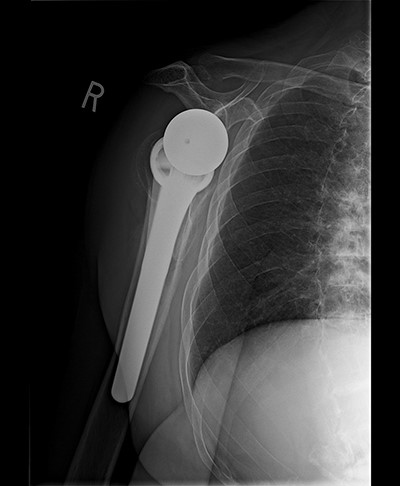

Surgically implanted devices included the DePuy France Delta Xtend Total Shoulder System, standard metaglene, standard glenosphere, cementless modular humeral stem, cementless modular epiphysis, standard humeral polyethylene cup, locking metaglene screw and non-locking metaglene screw.

Standard metaglene was positioned superiorly within the glenoid fossa to accommodate a 145° epiphysis and +4-mm lateralized glenosphere (Figs 4 and 5). There were no intraoperative complications.